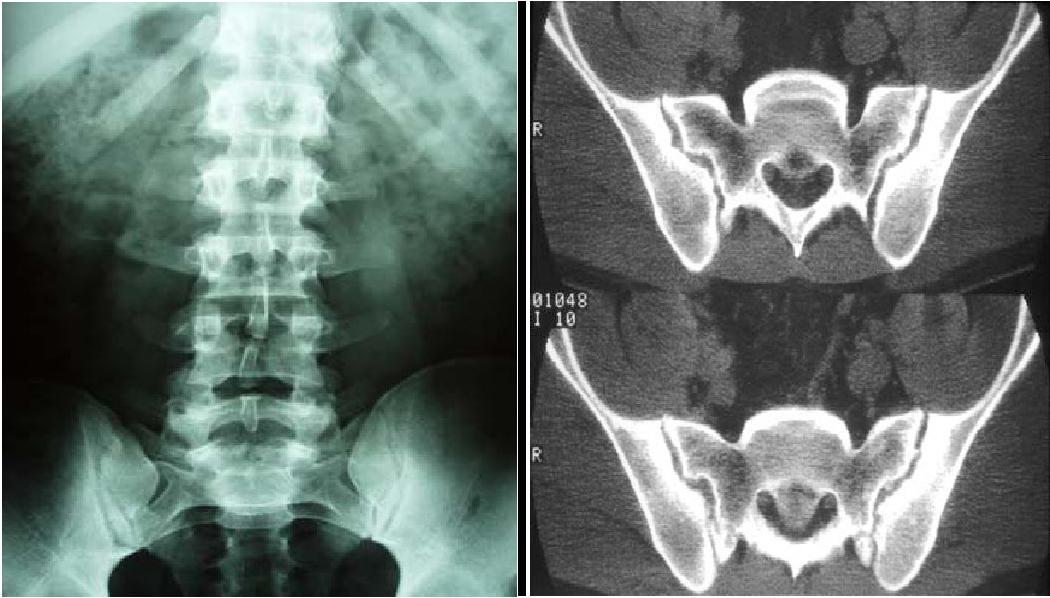

pelvianos o lumbares). El diagnóstico clínico se confirma por interrogatorio, y

palpación extra e intrarrectal. La coxigodinia se hace más evidente en la

posición sentada. RX una placa simple y otra placa sentado. El